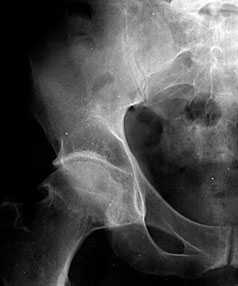

При компьютерной и магнитно-резонансной томографии обнаруживаются значительные дефекты суставной поверхности вертлужной впадины — от ее избыточных размеров (рис. 2) до фрагментации и смещения отломков. Определяются параартикулярные оссификаты, дополняющие картину протрузионного артроза тазобедренного сустава. Компьютерная томография дает возможность визуализировать состояние анатомических структур вертлужной впадины, их деформацию, пространственное расположение, величину диастаза между отломками, наличие дефекта в дне, направление и степень смещения крупных фрагментов, а также судить о массивности последних, что весьма важно для определения показаний к реконстмелкоочаговая оссификация, преимущественно по задней поверхности тазобедренного сустава. Наличие крупных обызвествлений ограничивает подвижность в суставе (причем в большей степени, чем инконгруэнтность), что сказывается на его статодинамической функции.

Рис. 2. Магнитно-резонансная томограмма левого тазобедренного сустава больного с посттравматической протрузией вертлужной впадины.